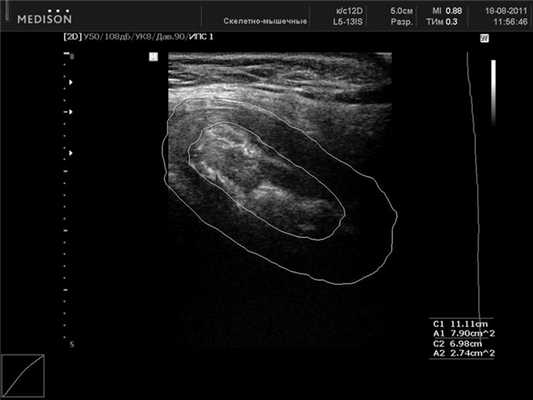

УЗИ ЛС проводили во фронтальной (рис. 3) Рисунок 3. Лонное сочленение. УЗ-сканирование во фронтальной проекции. и сагиттальной (рис. 4) Рисунок 4. Лонное сочленение без признаков дисфункции. УЗ-сканирование в сагиттальной проекции. проекциях при помощи трансабдоминального конвексного мультичастотного датчика с частотой 2-6 МГц или линейного датчика 5-12 МГц. Использование линейного датчика ограничено у тучных пациенток. Проводились измерения высоты, толщины симфиза и ширина его в верхней и нижней трети. Кроме того, мы исследовали площадь сечения межлобкового хрящевого диска (discus interpubicus), отношение этой величины к площади сечения всего сочленения, размер хрящевого пояса лобкового симфиза. Полученные результаты сравнивали с ранее полученными рентгенологическими и эхографическими данными. В качестве дополнительного метода исследования изучалась эхоплотность хрящевой межлобковой пластинки у женщин. Построение гистограмм плотности тканей ЛС у всех пациенток обследованных групп проводилось в одинаковых режимах сканирования. Гистограмма представляет собой тип диаграммы, отражающей распределение эхосигналов и позволяет сравнивать относительную плотность ткани по уровню градации «серой шкалы» в условных единицах. Учитывая максимальную зависимость получаемых значений эхоплотности от индивидуальных настроек аппарата, считали целесообразным использование не абсолютных показателей данного параметра, а относительных условных единиц. В основу математической обработки материала были положены непараметрические методы математической статистики с вычислением медианы интерквартильного размаха (значений 25-го и 75-го перцентилей) для каждого показателя. Сравнение групп наблюдения друг с другом производили с помощью ряда непараметрических критериев (Вилкоксона-Манна-Уитни, Смирнова, Фишера, χ 2 ).

Ультразвуковая структура лонного сочленения. При УЗИ в поперечном сечении в положении датчика на передней поверхности лона лобковый симфиз представляет собой неоднородное, средней эхогенности образование, расположенное между эхотенями лобковых костей. В центре симфиза визуализируется более эхоплотное «ядро» ЛС, неоднородное за счет чередования участков различной эхогенности. «Ядро» окружено более гипоэхогенным хрящевым ободком. Над ним визуализируется в большинстве случаев lig. pubicum superius. На данных ультразвуковых срезах возможно измерить ширину ЛС как по верхнему, так и по нижнему краю. Ориентиром служат лобковые кости.

При сагиттальном сканировании ЛС представляет собой овальное образование неоднородной структуры с четко выделяемым «ядром», включающим гипер- и гипоэхогенные участки. По наружной поверхности хрящевого пояса в большинстве случаев удается дифференцировать по верхнему краю lig. pubicum superius, снизу - lig. arcuatum pubis, спереди - lig. fibrosum anterior и сзади - lig. fibrosum posterior. Они служат ориентирами при измерении размеров лобкового симфиза. При сравнении ультразвуковой картины с данными проведенных ранее (М.Ф. Айзенберг, 1962) морфологических исследований можно предположить, что гипоэхогенный ободок симфиза является гиалиновой частью хрящевого диска, гиперэхогенное «ядро» - участки замещения фиброзным хрящом. В структуре хрящевого пояса могут обнаруживаться гиперэхогенные включения округлой или неправильной формы, являющиеся, вероятнее всего, зонами оссификации (см. рис. 4). Сагиттальные ультразвуковые срезы у края правой или левой лобковых костей представляют собой более или менее однородную овальную гипоэхогенную структуру ткани хрящевого диска с гиперэхогенным (дающим тень) краевым срезом лобковой кости. Линейные размеры ЛС у женщин при ультразвуковом исследовании представлены в табл. 1.

У пациенток с дисфункцией ЛС при сагиттальном сканировании хрящевого диска обнаружены изменения в структуре фиброзной части хрящевой межлобковой пластинки в виде неправильной формы очагов с гипо- и анэхогенной структурой. Размеры и степень выраженности не всегда были прямо пропорциональны тяжести клинической симптоматики «симфизита». Для оценки эхографической картины были произведены измерение площади фиброзной части хрящевого диска, площади каждого очага с помощью функции обводки линейного контура, расчет суммарной площади измененных участков, измерение эхоплотности патологических зон (рис. 5). Рисунок 5. Лонное сочленение при дисфункции. УЗ-сканирование в сагиттальной проекции. Средние значения эхоплотности очагов составили 21,4 усл. ед. (13,2-32,0) при средней величине эхоплотности фиброзного «ядра» лонного сочленения у беременных без клинических признаков дисфункции ЛС - 96,1 (73,1-112,0) усл. ед. Таким образом, выявлено очаговое снижение эхоплотности ткани фиброзного хряща в 4,4 раза по сравнению с таковой у беременных, не имеющих клинических признаков дисфункции ЛС. Данное исследование позволяет предположить, что в основе нарушения функции ЛС во время беременности лежат морфологические изменения, связанные с течением самой беременности, а травматические повреждения ЛС в родах наступают как следствие первичных изменений структуры тканей. Формирование гипоэхогенных зон в структуре фиброзного хряща связано, вероятнее всего, с повышением гидрофильности тканей за счет воспалительных или аутоиммунных нарушений макроорганизма.